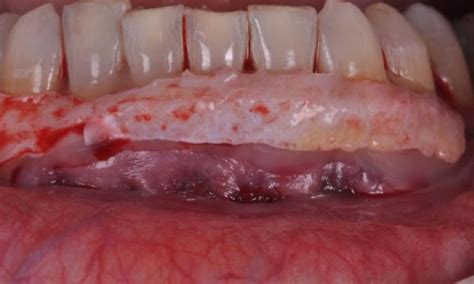

Cuando hablamos de encías retraídas nos referimos a un desplazamiento del tejido gingival que provoca una sobreexposición del diente. Las encías se desplazan hacia arriba en los dientes superiores y hacia abajo en los dientes inferiores dejando al descubierto parte de la raíz dental.

Esto no solo afecta a la estética, sino que también compromete la protección natural de los dientes, aumentando la sensibilidad y el riesgo de enfermedades.

Ejemplo de encías retraídas, mostrando la exposición de la raíz del diente.